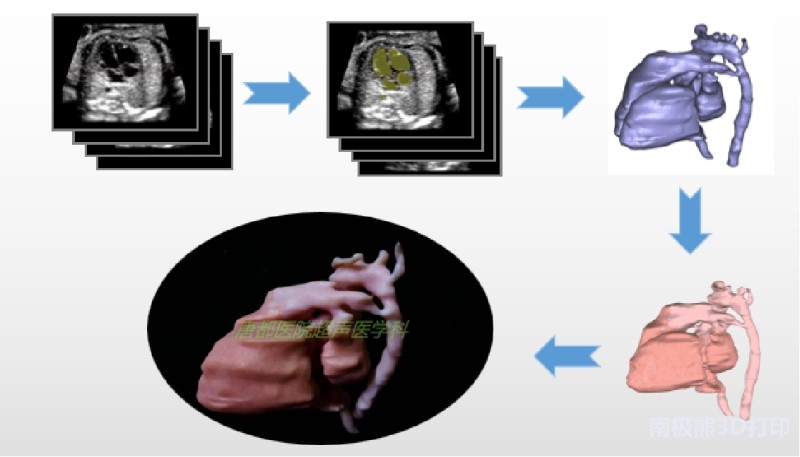

近日,空军军医大学唐都医院超声医学科3D打印研究中心完成了基于超声影像数据的胎儿心脏多色3D打印。该模型完整地呈现了包括胎儿心脏四腔、主动脉弓、降主动脉、动脉导管、肺动脉、上腔静脉、下腔静脉、无名静脉以及卵圆孔、气管和左右主支气管等解剖结构,成功地将胎儿心脏及其周围大动脉、静脉和气管之间的空间结构关系精准还原,最终利用光固化多色打印技术清晰地展现出来。

胎儿心脏模型整体体积相比于实际大小放大了8倍,模型的长宽高分别约为33 mm、25 mm和24 mm。此次三维建模历时3小时,色彩贴图6小时,3D打印及后处理约8-9小时完成。

该技术的难点在于建模时对超声图像的识别和把握,必须将胎儿心脏与周围的大血管和气管等结构准确地三维重建。通过三维重建,能够将解剖结构实体化,更清晰直观地展现异常的解剖结构以及它们之间的空间位置关系。通过实体模型,医生能够更加直接地进行病情的讨论和治疗方案的设计,必要时还可以利用模型进行手术模拟,大大提高工作效率。

基于超声数据三维建模并3D打印胎儿心脏是医工结合的又一典范,是3D打印与超声医学学科的完美结合。